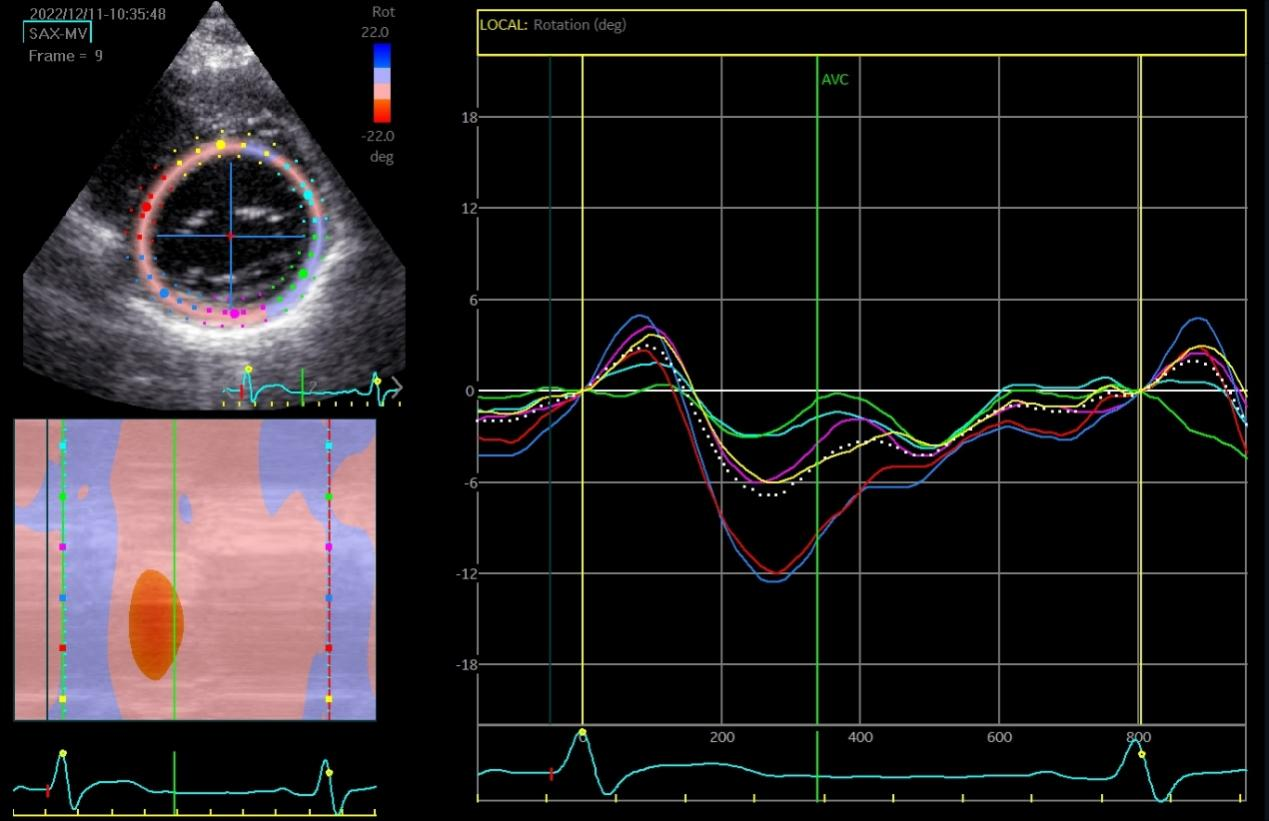

The speckle tracking echocardiographic data before and after the marathon are exhibited in Table 3. Before marathon (as baseline), the LT runners group showed significantly higher absolute values of apical rotation, LV twist, LV torsion and LV UTR, but a significantly lower absolute value of GLS, compared to the other groups (Table 3, p < 0.05). The GLS values were -19.39 ± 2.68, -21.56 ± 2.56, -21.04 ± 2.26 and -21.52 ± 2.35 in LT runners, ST runners, MET runners, and controls, respectively (Table 3). 1 hour after marathon, the absolute value of GCS was significantly lower in the LT runners group compared with the ST and MET runners (Table 3, p < 0.05). LV twist and LV torsion demonstrated similar trends across all 3 amateur marathon runners groups 1 hour after marathon, with no significant differences observed (Table 3, p > 0.05). Compared to baseline measurement, the absolute value of all speckle tracking echocardiographic parameters was decreased 1 hour after marathon in all amateur marathon runners (p < 0.05), and returned to baseline 4 days after marathon, showing no statistical differences before and 4 days after marathon (Table 3). Δ GLS, Δ GCS, Δ Apical rotation, Δ LV twist, Δ LV torsion, and Δ LV UTR were markedly elevated in the LT runners group relative to the ST runners and the MET runners groups (Table 4, p < 0.01). Basal rotation was similar in all 3 amateur marathon runners groups (Table 4). The apical rotation image and basal rotation image and left ventricular torsion diagram (speckle echocardiography) of the amateur marathon runners in the LT group can be seen in Figure 1-3.

Figure 1 Apical rotation image (speckle tracking echocardiographic) in LT group amateur marathon runners. LT, long-term.

Figure 2 Basal rotation image (speckle tracking echocardiographic) in LT group amateur marathon runners. LT, long-term.